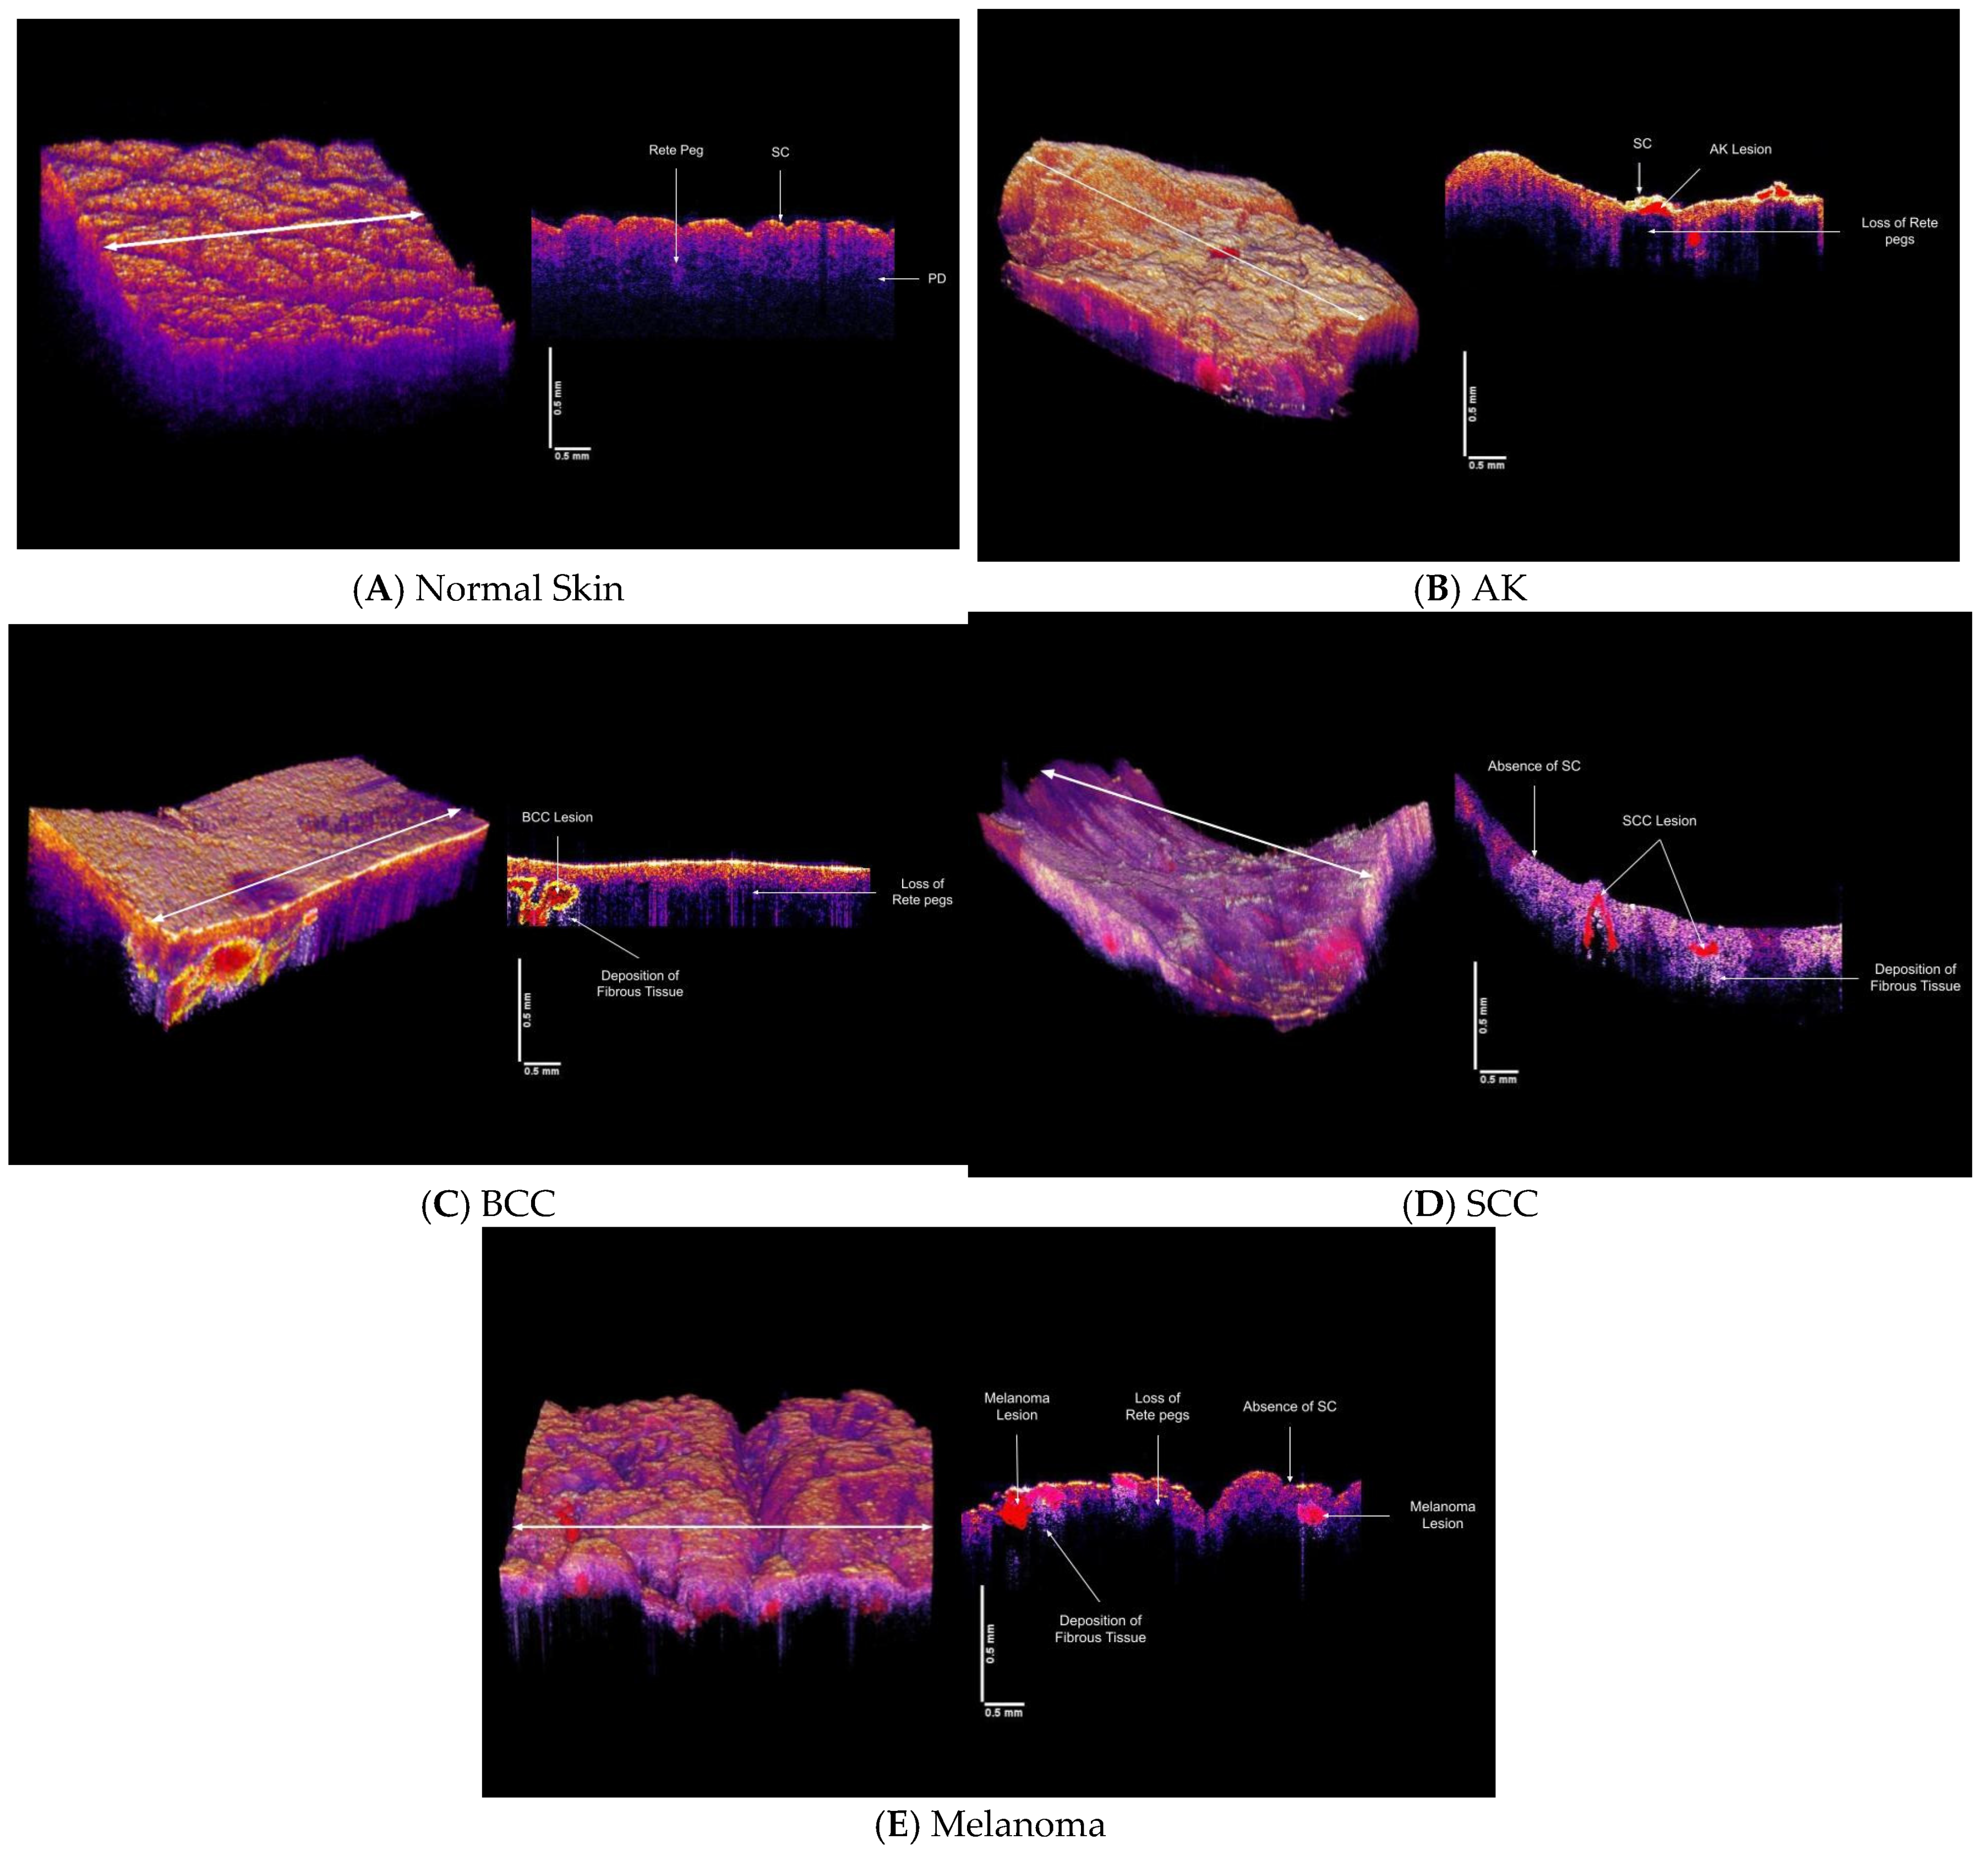

3.3. Virtual Biopsy Reconstructions of Normal Skin, AK, BCC, SCC and Melanoma